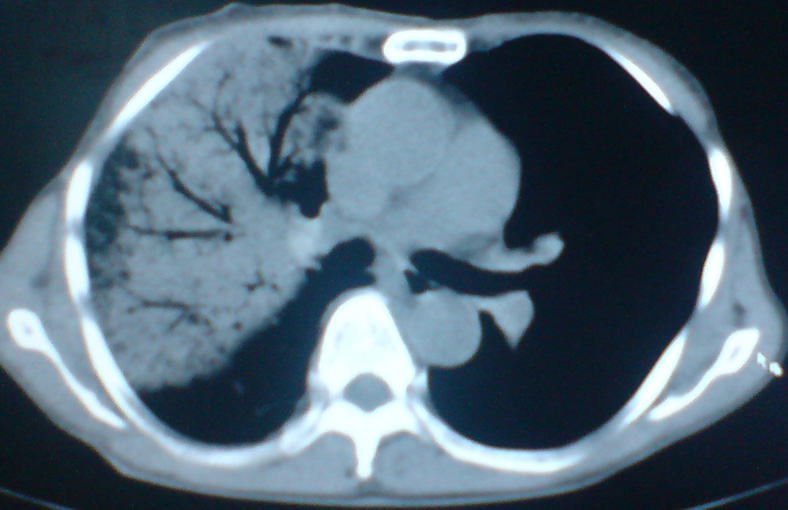

患者,女,60岁,右侧胸痛、咳嗽两个月。

支持:大叶性肺炎,病灶内支气管走行自然,无僵直及粗细改变,建议抗炎治疗后复查!